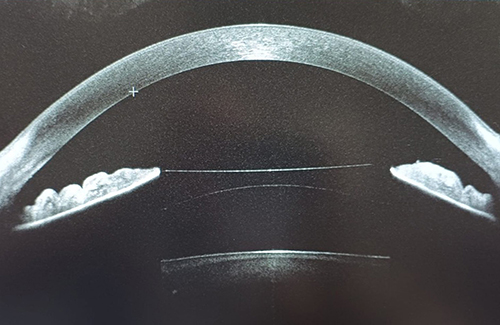

• Lenti fachiche: impianto di una lente all’interno dell’occhio, davanti o dietro l’iride, mantenendo il cristallino naturale. Indicate soprattutto per difetti elevati o quando il laser non è consigliabile.

• Studio della cornea (topografia e pachimetria)